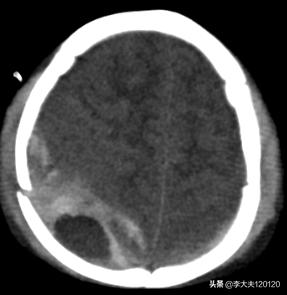

三个小时后,患儿意识障碍加重,立即复查头颅CT:血肿量增加。

与家属沟通后,立即将患儿送往手术室,全麻状态下,行“右顶枕部开颅硬膜外血肿清除术”。

术后CT图片